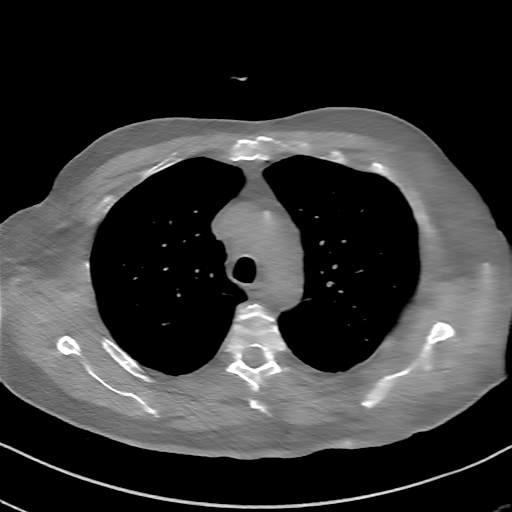

Datasets. We first train and test models on the “2016 NIH-AAPM-Mayo Clinic Low Dose CT Grand Challenge” dataset [14]. Specifically, we choose 1,746 slices of five patients for training and 1,716 slices of another five patients for testing. To further show our models’ generalization capability, we test our models on 1,958 slices of four patients chosen from the COVID-19 dataset, and 1,635 slices of six patients from the LIDC dataset [4]. The two datasets are also composed of chest CT images but from different scenarios and machines, which constitutes good choices for testing the generalization capability. For the generalizability experiments, we have added additional HU value shift to the latter two datasets, which brings about similar distribution deformation. All the experiments are conducted with Fan-Beam Geometry and the number of detector elements is set to 800. Besides, we add mixed noise, composed of 5% Gaussian noise and Poisson noise with an intensity of , to all simulated sinograms [30].

Qualitative Results Comparison. We also visualize the reconstruction results of these methods on AAPM-test and COVID-test datasets. As in the first three rows of Fig. 4, the reconstructed images from ours and retrained MetaInvNet show the best visualization quality on AAPM-test set across different angle numbers. Besides, our results show sharper details with the additional utilization of in the projection domain. When testing the reconstructed image on the COVID-test set, our result also gives sharper details but with more artifacts since the data distribution is very different. Although HQS-CG has achieved better quantitative results on the COVID-test dataset, the reconstructed image of their model in the fourth row is even smoother than FBP.